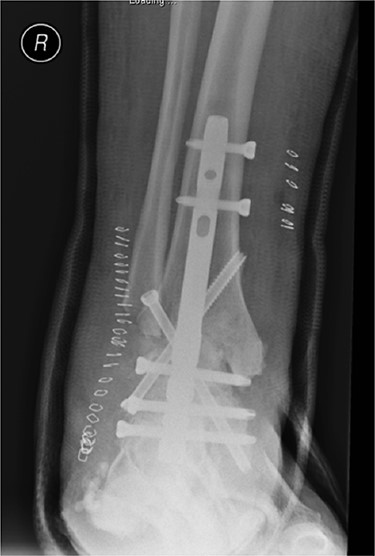

In May 2015, he had a complex midfoot reconstruction, but his foot continued to drift into varus. This was complicated by an infected ulcer on the lateral aspect of midfoot (Fig. 3). Wound infection progressed to osteomyelitis, and in May 2018, he had a hindfoot reconstruction with fusion of tibiotalar and subtalar joints using a Cerament-V-coated hindfoot nail (Figs 4 and 5).

Anterior–posterior radiograph of right ankle demonstrating tibiotalocalcaneal fusion using a hindfoot nail and screws.